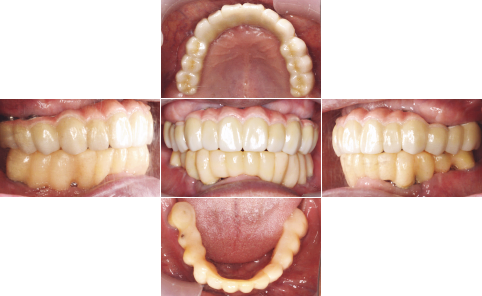

| 治療前 | 治療後 |

| 上顎はいつ抜けてもおかしくない状態であったため、直ちにAll-on-4を施術しました。 下顎も重度の歯周病で状態は良くありませんでしたが、患者様の希望もあり、抜歯せず、現在経過観察中です。 |